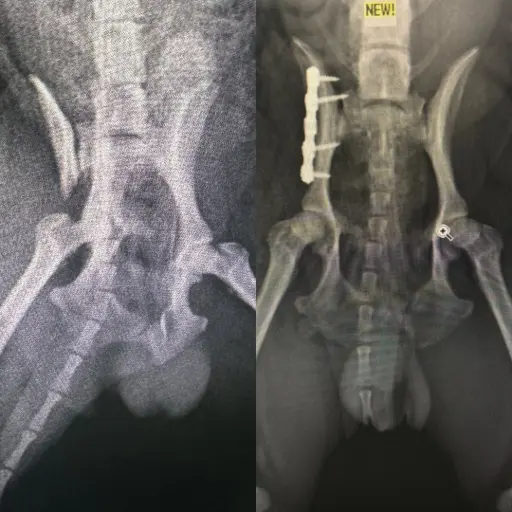

Köpeklerde Diz Kapağı Çıkığı, Çapraz Bağ Kopuğu, Kalça Çıkığı ve Kırık Ameliyatı

Uzmanlık alanları arasında bacak ve kol kırıkları, travma sonucu kalça kırıkları, yüksekten düşme sonucu oluşan travmalar, kranial ve ön çapraz bağ kopmaları, parçalı pelvis kırıkları, eklemden kırıklar, kalça çıkıkları, distal radius ve ulna kırıkları ile doğumsal kalça problemleri gibi birçok ortopedik vaka yer almaktadır.